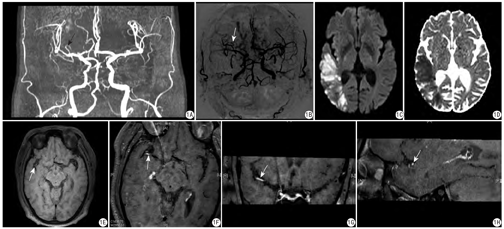

44例患者中共检出66个斑块,其中47个为明显强化,13个为轻度强化,6个为无强化(图1)。

急性/亚急性期责任斑块、慢性责任斑块、非责任斑块数量分别为29个、20个、17个;3组的斑块强化程度、管腔狭窄程度差异有统计学意义(χ2=94.990,P<0.001 ;χ2=94.802 ,P<0.001);斑块强化和管腔狭窄的共同作用在3组中差异有统计学意义(χ2=6.676,P=0.003)。见表2。